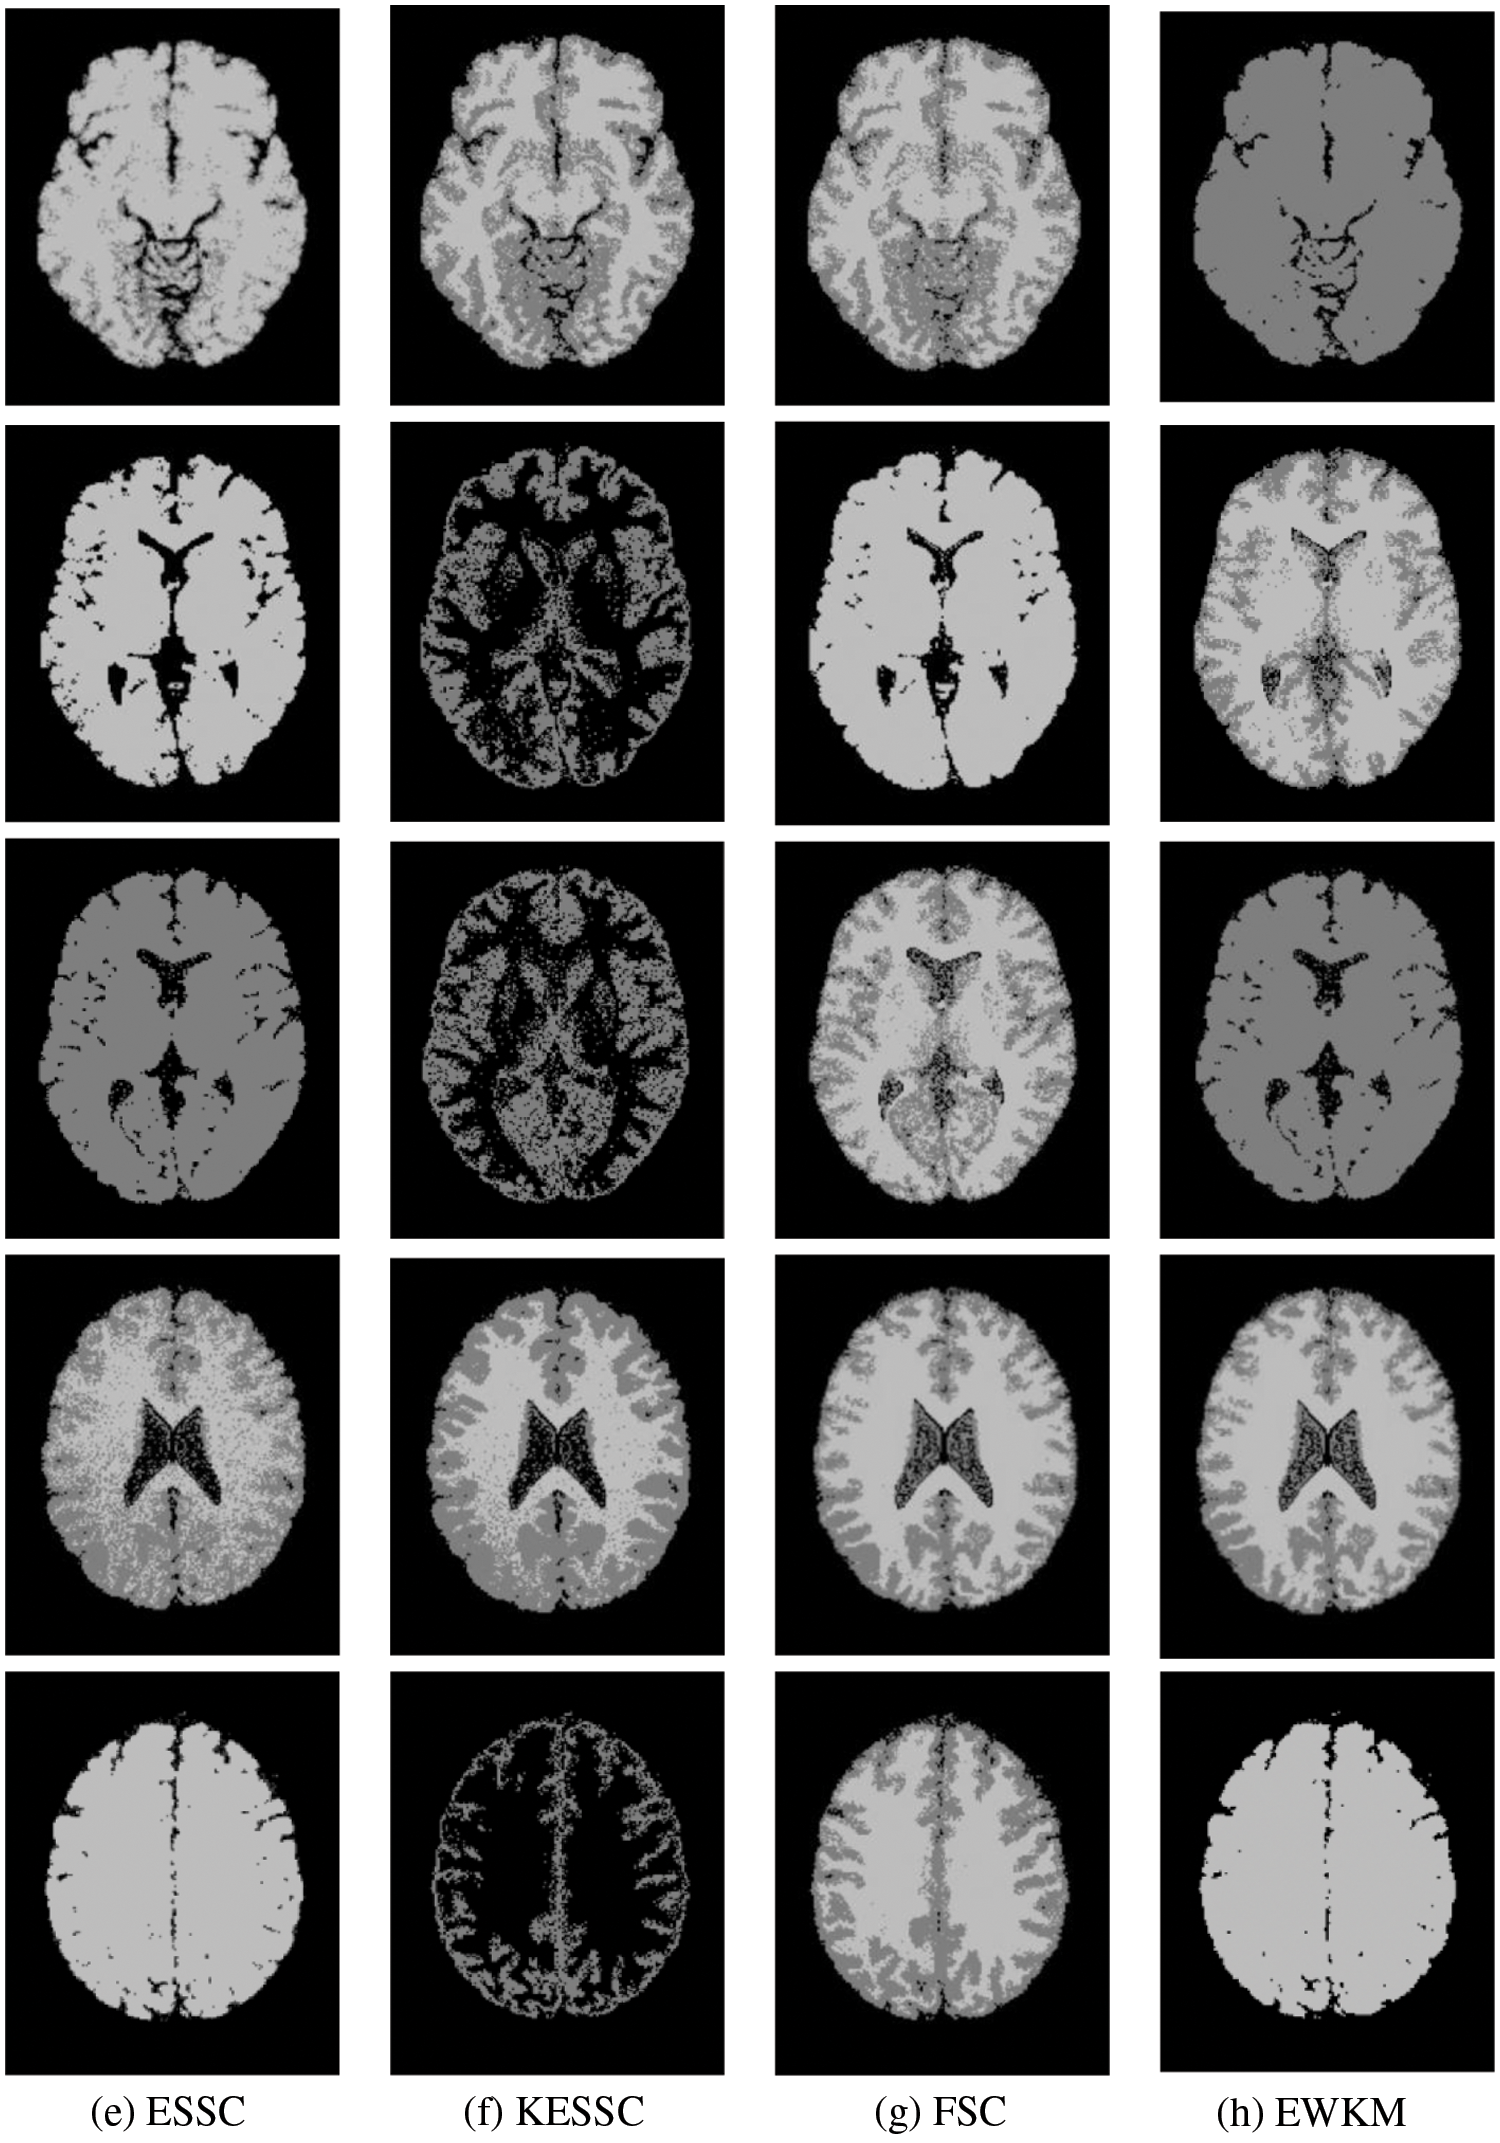

Taking the normal brain database as an example, multiple noise levels were provided, and the noise level pn0 = 0%, 1%, 3%, 5%, 7%, 9%. To verify the anti-noise performance of the algorithm, the highest noise level was selected, and 5 brain images were selected to verify the segmentation effect of the algorithm compared with other soft subspace clustering algorithms. The mode = T1, protocol = ICBM, phantom name = normal, section thickness = 1 mm, noise = 9%, and INU = 0%; brain images of 62 pages, 75 pages, 83 pages, 96 pages, 107 pages were selected. Cluster segmentation was performed for 0 = Background, 1 = CSF, Cerebrospinal Fluid, 2 = Gray Matter, and 3 = White Matter. The effect of segmentation and clustering is shown in Fig. 3:

Figure 3: The segmentation result of the T1-weighted simulated brain MR image, (a) depicts the original image, (b) depicts the standard segmentation result graph for evaluation calculation, (c) depicts the segmentation effect of the GAESSCND algorithm proposed in this paper, (d) depicts the segmentation effect of the ESSCND algorithm, (e) depicts the segmentation effect of the ESSC algorithm, (f) depicts the segmentation effect of the KESSC algorithm that guides the kernel function, (g) depicts the segmentation effect of the FSC algorithm, and (h) depicts the segmentation effect of the entropy weighted EWKM algorithm

In Fig. 3, Column (a) is the clustering algorithm proposed in this paper, and the segmentation effect is obviously better than that of other soft subspace clustering algorithms (b–h). In this chapter, the Rand Index (RI) [45], normalized mutual information (NMI) [46] and accuracy indices are used to evaluate the clustering effect, where RI and NMI are calculated by Eqs. (16) and (17), respectively.

Comparing the data obtained from Table 2, the segmentation effect of the GAESSCND algorithm is very similar to the standard segmentation. The GAESSCND algorithm proposed in this section is compared with four existing soft subspace clustering algorithms, ESSC, EWKM, FSC, and KESSC with a kernel function, and ESSCND with generalized noise detection, where the FSC algorithm is a fuzzy weighted soft subspace clustering algorithm and the EWKM algorithm is an entropy weighted soft subspace clustering algorithm. The ESSC algorithm combines intraclass and interclass information, and the rest of the improved soft subspace clustering algorithms select reasonable parameters in a larger range. The evaluation indices are chosen in 3 ways to determine the noise immunity of the GAESSCND algorithm for noisy MR images. From the displayed visual effect and the 3 evaluation indices, GAESSCND has good noise immunity, and the clustering effect is similar to the standard segmentation. Compared with other soft subspace clustering algorithms, which are not effective in segmenting boundaries and dividing brain regions, the GAESSCND algorithm can clearly divide brain white matter, brain gray matter, cerebrospinal fluid [47] and background regions well so that the problem of noise in MR images of the brain can be handled well.